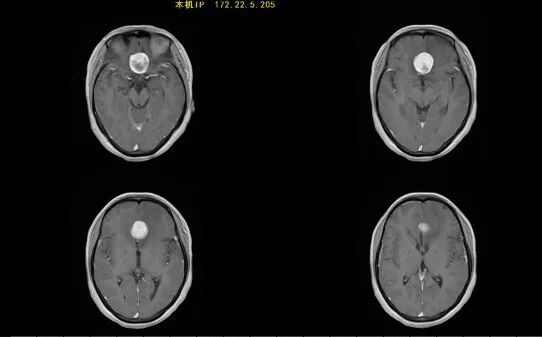

55歲的趙先生(化名)突然癲癇發(fā)作1次,到醫(yī)院做了頭部磁共振,檢查結(jié)果提示是腦腫瘤,考慮膠質(zhì)瘤。醫(yī)生建議他盡快住院進(jìn)行手術(shù)治療。得知要開顱手術(shù),趙先生心生畏懼,考慮癲癇僅發(fā)作一次,也沒(méi)有其他不適,決定回家再觀察一下。然而好景不長(zhǎng),過(guò)了數(shù)月,趙先生回到醫(yī)院復(fù)查,結(jié)果讓他悔恨莫及!此時(shí),腫瘤已經(jīng)明顯增大。趙先生立刻來(lái)到惠州三院神經(jīng)醫(yī)學(xué)中心神經(jīng)外科尋求治療,并順利做了手術(shù)。

趙先生頭部磁共振(箭頭白色區(qū)域處為腫瘤)